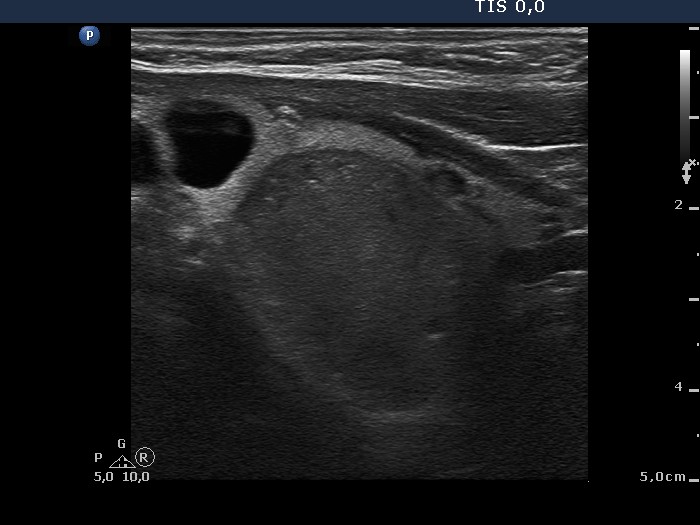

Hashimoto's thyroiditis without any nodule (histological diagnosis) - case 1520 |

The coexistence of tiny punctate granules and similarly bright lines is the hallmark of connective tissue. There is a brighter and relatively large granule in the ventral small lesion in the upper image which might be either a punctate echogenic focus or a sign of fibrotic changes.